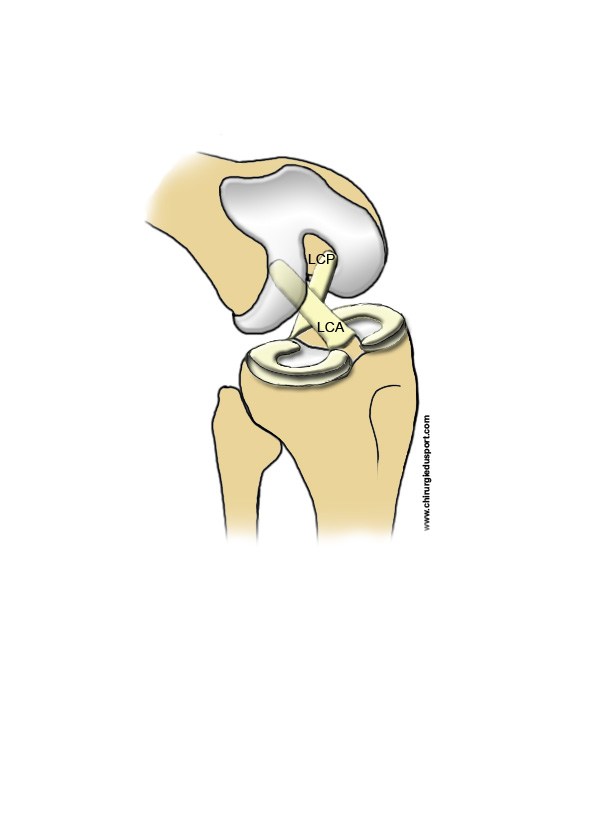

En haut se trouve le fémur, l’os de la cuisse. En bas, il y a le tibia, l’os de la jambe. Le bas du fémur est plutôt rond et le haut du tibia apparaît beaucoup plus plat. Les ménisques sont des petites cales situées entre les deux os du genou.